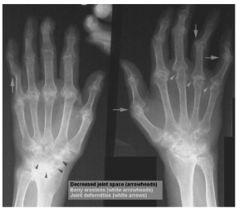

XR of RA

soft tissue swelling

angular deformity - subluxation

carpal destruction

periarticular erosions

osteoporosis/osteopenia

juxta-articular osteopeni

reduced joint space